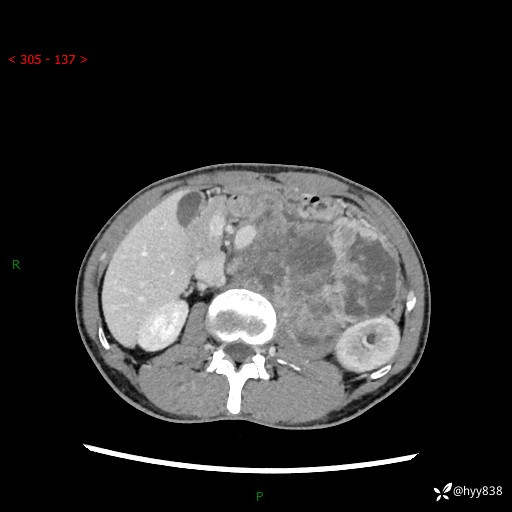

简要病史:患者无明显诱因出现左侧下腹及左侧腰背部疼痛,为间歇性隐痛,我院行胃肠镜检查,提示慢性非萎缩性胃炎,予以口服药物治疗,效果欠佳,后仍觉腹痛不适,遂至当地中医医院就诊,行彩超提示左肾积水及左肾实质性占位,遂来我院泌尿外科就诊

腹部CT平扫+增强